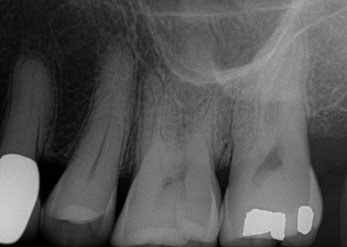

One of the best ways to improve your oral health is to understand its current state and how its changed since your previous appointments. For this reason we have invested in advanced computer systems and digital imaging software so your records don't have to be a secret or difficult to understand.  During your appointment we will discuss diagnostic images from your current and previous appointments, so you understand any minor changes worth monitoring or major problems that require intervention. Your images are presented to you on large 34" monitors that make it easy for you to see how healthy your mouth is, or any damages. We also keep diagrammed digital charts that allow for you to easily see the type and location of previous work you have completed.